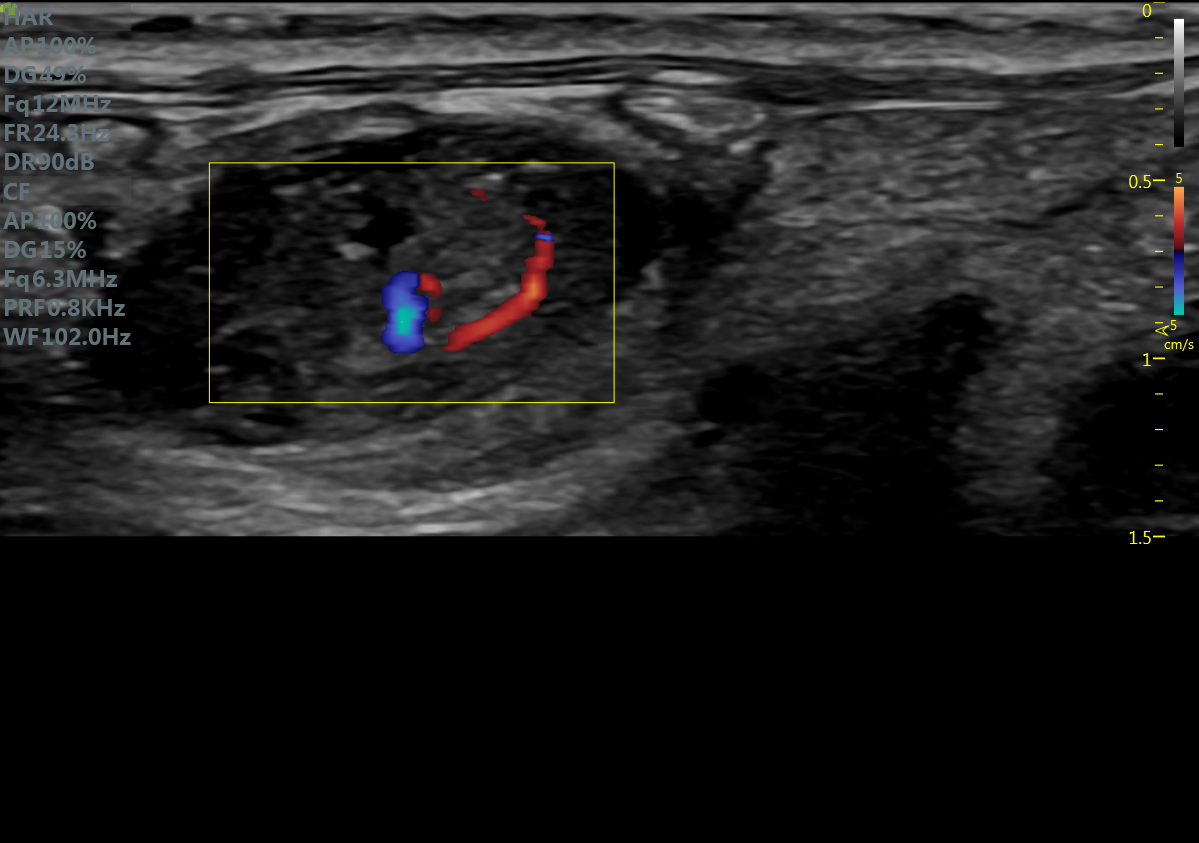

RF Flow充盈不外溢 Xcen超高频浅表显影